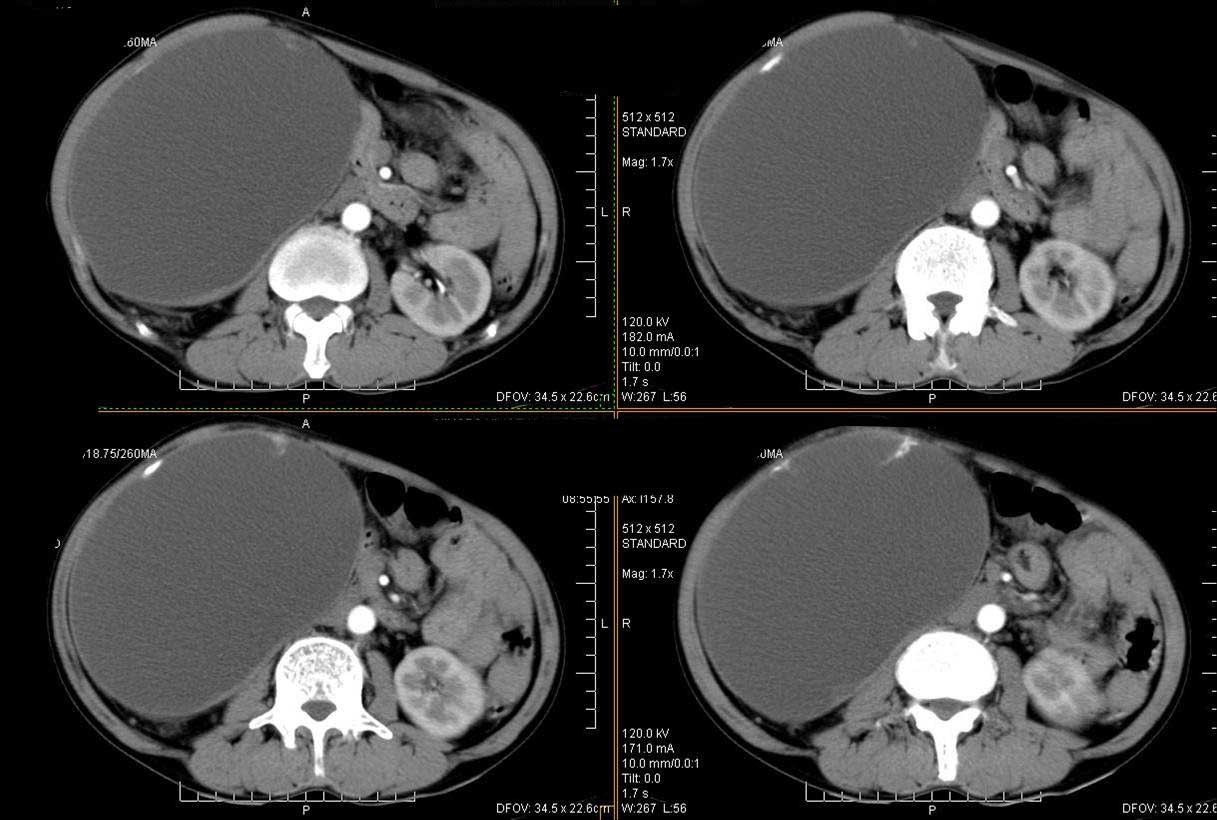

ct值测量

平扫

动脉期

门脉期

右肾脏巨大囊样影、囊壁有钙化,囊样影轻度强化有软组织成份。不除外畸胎瘤可能。

巨大囊性肿块,囊壁较厚有强化,有团片状钙化,病灶内下方灶内见片絮状高密度影,增强有轻中度强化,考虑囊性肾癌可能性大

右肾上部巨大的囊实性影,实性部分轻度强化。壁有钙化。考虑右肾囊腺癌。右肾盂积水。